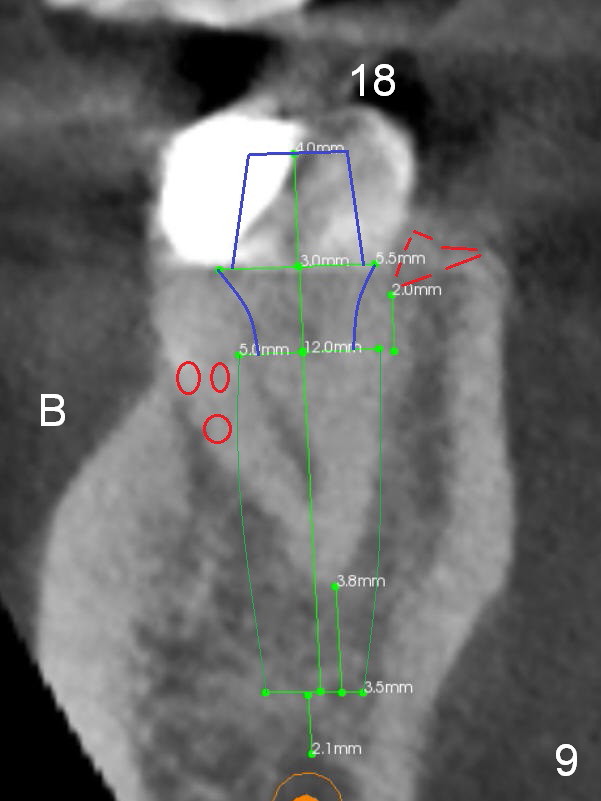

A 35-year-old lady (YL) has periodic nocturnal pain of the lower left quadrant.  There is open buccal margin at the abutment of #18 (Fig.1 (from panoramus)).  When the pontic and the retainer are removed (Fig.2), there is a large buccal subgingival carious lesion at the tooth #18.  The latter has 2 roots, although close to each other.  If the extraction turns out to be difficult, section the tooth (Fig.3 red line (no antibiotic)).  To avoid contacting the tooth #17, place an implant at the mesial socket of #18 (Fig.5,7).  Although it appears that the tooth #20 has no periapical radiolucency (Fig.6,7), the crown will be removed for diagnosis.  A 3-unit provisional will be fabricated after an implant is placed at #19 (Fig.7,8) in the same appointment.